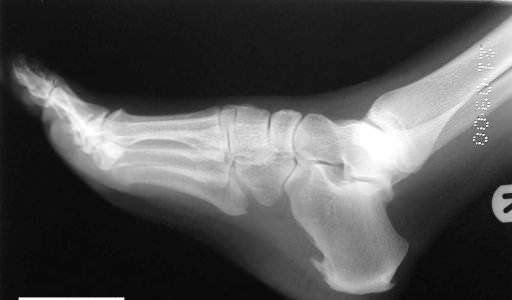

Esporão de Calcâneo: Por que se confunde tanto com Fascite Plantar?

Entenda por que este achado comum em exames de imagem raramente é a causa da dor e onde buscar o tratamento correto. Tempo de leitura: 18 min